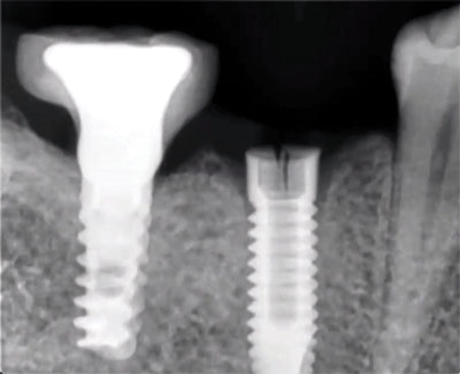

Implants with internal hex connections are more prone to failure at the connection than those with external hex connections.28 This is related to the thickness of the metal at the thinnest point between the internal surface of the interface and the external surface at the crestal area of the implant. When overloaded, implants with an internal hex connection may present with fractures at the points of the hex.29 These points are where the metal is the thinnest at the crestal portion of the implant and where stress is concentrated during overloading. This is less problematic in wider diameter implants because the metal is thicker in this area of the implant; however, in standard or narrow diameter implants, fracture may result, causing catastrophic failure of the implant (Figure 1). This may also occur in other internal implant connection types, such as trilobe connections, especially when the crestal thickness of the implant is minimal, leading to fracture of the coronal aspect of the implant (Figure 2). Implants with conical connections are not immune to potential fracture in this area, and the thin walls of some standard or narrow diameter models may split even without the isolated stress points observed in internal hex-, trilobe-, and octagon-type connections (Figure 3).30 Sometimes, fractures of implants at the coronal aspect are not clinically visible but, instead, are identified radiographically either after a patient complaint of pain in the area, due to the presence of soft-tissue inflammation, or during a routine examination with no patient complaint (Figure 4).

(1.) Fractures at the points of the internal hex connection where the metal is thinnest resulting in catastrophic implant failure.

Figure 1